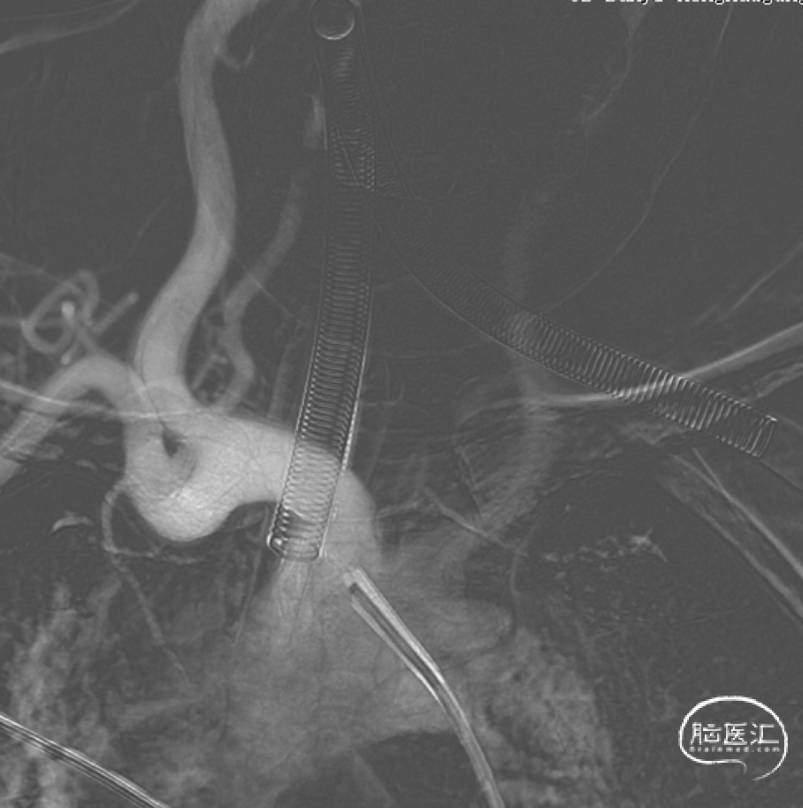

颈内动脉迂曲,8F 100cm Guiding+6F Navien过弯提供支撑。Sychro 14带SL-10平顺进入同侧A2远端,Echelon-10 塑形45°进入动脉瘤(如下视频)。

支架释放。可见A2段血管曲度几无改变。Echelon管头位置几无变化(如下视频)。

术毕。填塞率33%。术前术后对比,动脉瘤残腔消失,瘤颈分支保存。